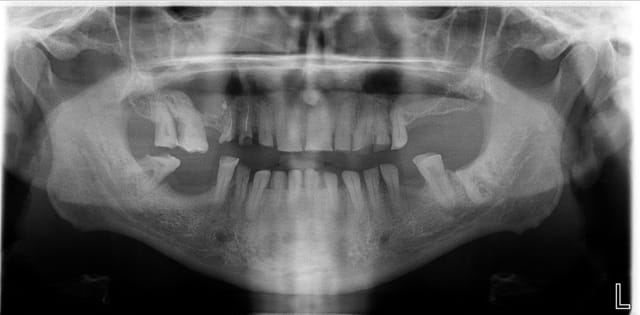

Pour le moment je vous poste l'OPT. Si ce cas vous interesse j'essaierai de poster régulièrement l'évolution.

Pas d'IC me semble compliqué dans le cas présent: quand on voit la pano, on se dit qu'il ne doit pas y avoir gd chose qui dépasse des gencives.

Il faut quand même un minimum de rétention pour pouvoir se contenter de tailler sur dents vivantes; sur les incisives, je ne vois pas comment s'accrocher sans mettre de tenon: c'est plat, la dentine doit être hyper-minéralisée ce qui ne facilite pas le collage... et la hauteur de couronne clinique ne doit pas dépasser 2mm.

-je dois gagner en couronne clinique : bio et tfm (de plus les dents sont bien sensibles, je ne veux pas prendre de risque sous un tel bridge)

- bridge de 17 à 11 et 21 à 26. exodontie éventuelle des 14 15. cantilever 26.

De la même manière, tu n'arriveras jamais à gérer l'occlusion et la DV si tu ne réalise que le haut d'abord. Pour tester ta DV, tu auras besoin de l'avoir complètement relevée d'abord, donc au moins les provisoires haut et bas: après, rien ne t'empêchera de réaliser les définitives maxillaires en premier, avec une empreinte de ton antagoniste.